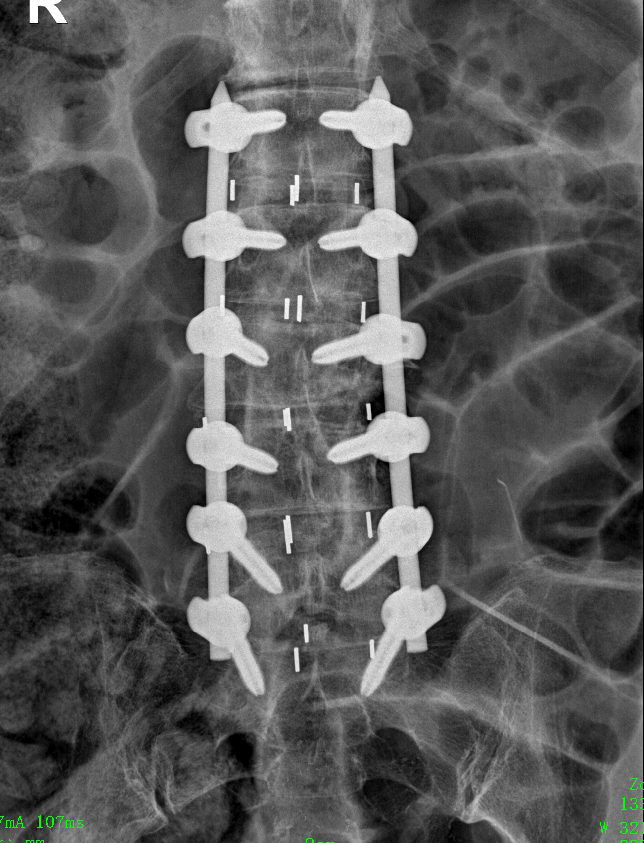

術(shù)后,患者經(jīng)過一周的休養(yǎng),身體狀況逐漸穩(wěn)定,隨即進(jìn)入第二階段手術(shù)。在腰背部,醫(yī)生采用經(jīng)皮微創(chuàng)技術(shù)置入12枚鈦合金椎弓根螺釘,進(jìn)一步矯正殘存的側(cè)彎畸形,且同時(shí)形成堅(jiān)強(qiáng)的內(nèi)固定,為脊柱的長期穩(wěn)定提供了有力保障。